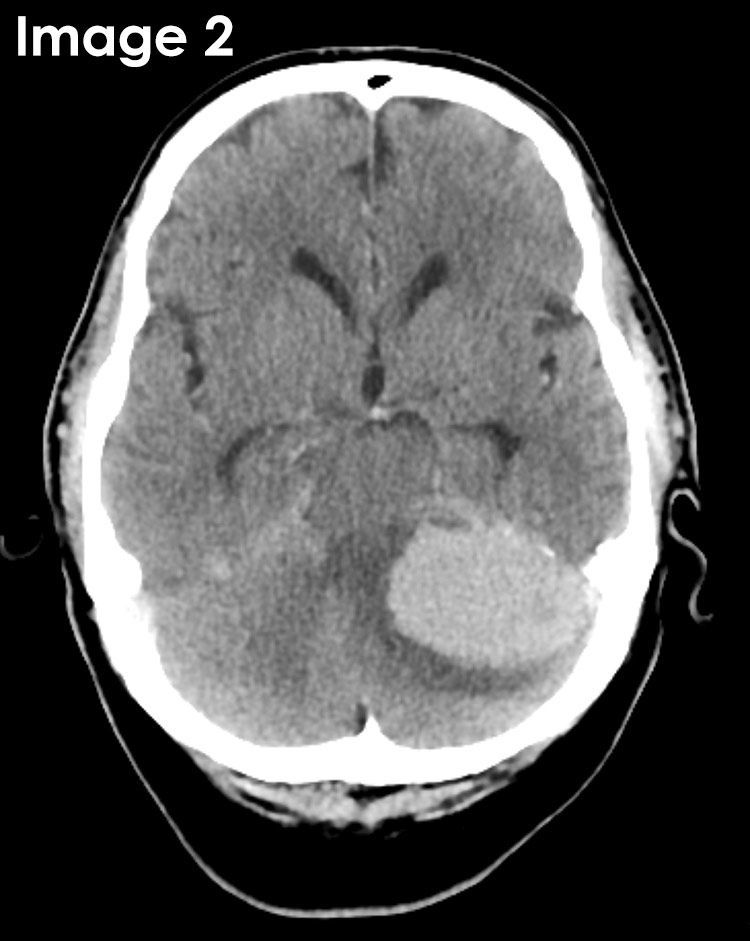

@RadMasterclass

Radiology Masterclass

5 months

CT BRAIN QUIZ: Non-contrast CT. History of hypertension & sudden left facial droop. What does the image show? A: Subarachnoid haemorrhage B: Subdural haemorrhage C: Intraventricular haemorrhage D: Intracerebral haemorrhage E: Enhancing mass Start Quiz https://t.co/ATFl8YktNe

16

20

103